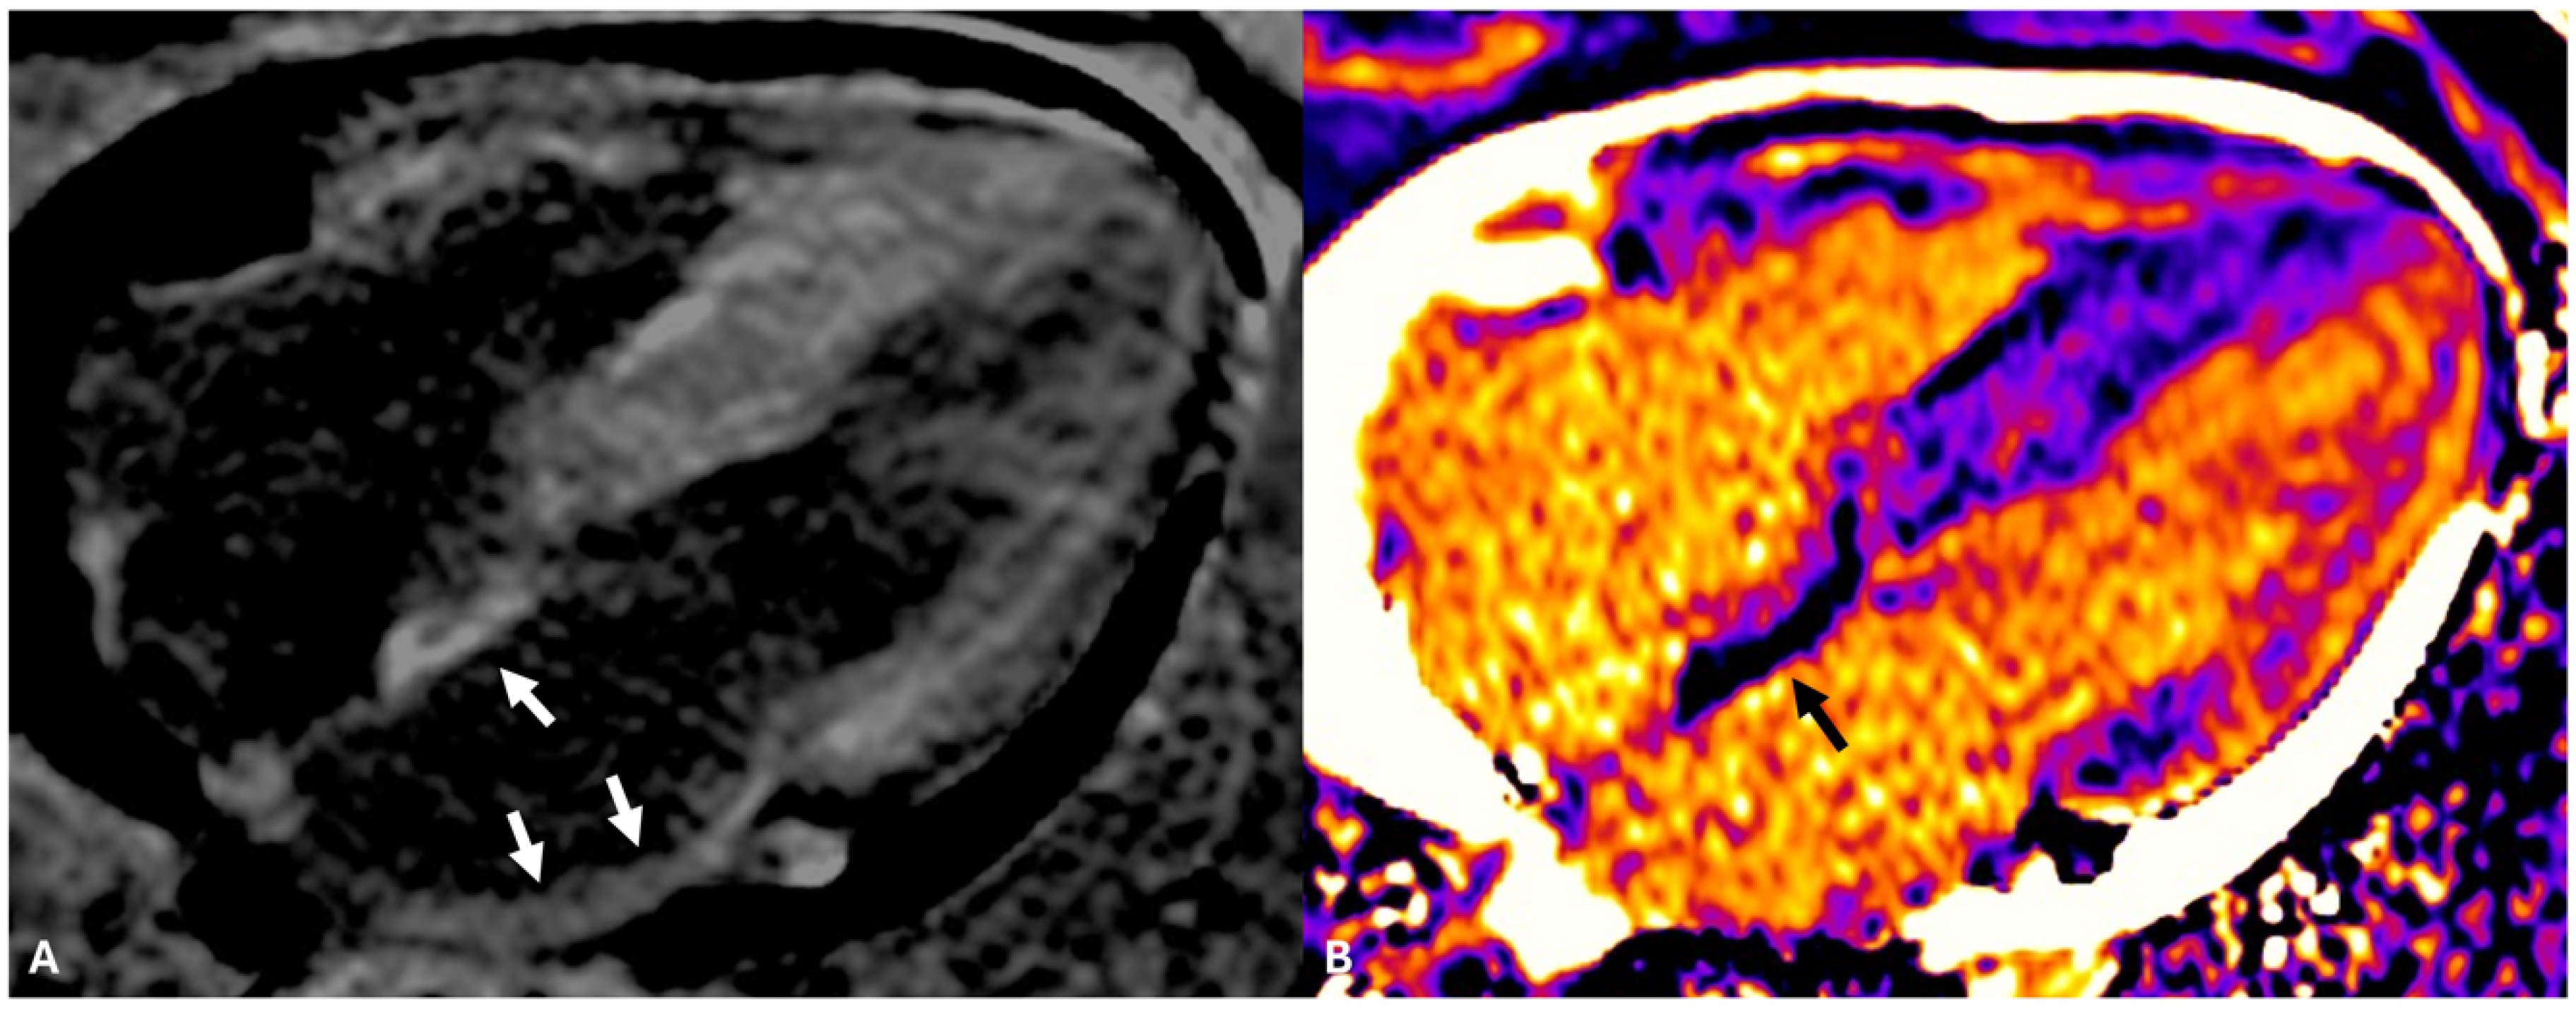

4. Atrial CMR Imaging for LA Fibrosis Evaluation: A New Frontier

6. Substrate AF Ablation Using CMR-Guided Approach

7. Limitations of DE-CMR in Detecting Atrial Fibrosis